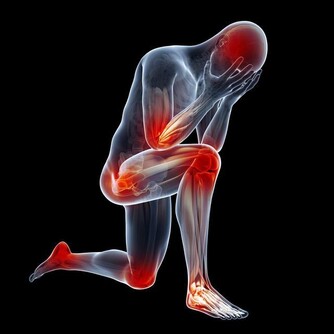

但從西醫的角度來講,腰痛更多的可能是感染,還有就是是結石,當然過於疲勞也可能會發生腰痛。

此外,外部損傷也是腰痛的一個重要原因。骨頭損傷最常見的就是椎間盤突出滑脫,多發生在很多人彎腰提起重物的時候。

上了年紀的人,特別容易引起骨質增生,這些情況都可以引起椎間盤損傷、脫出甚至是裂開。這也是常見的腰痛。

腰痛在泌尿外科,最多見的是結石和泌尿系感染這兩種。特別厲害的腰痛,我們稱之為“腎絞痛”。

一般不太厲害的腰痛,就覺得腎區有點悶痛,或者體表位置引起疼痛,這就要看具體病人的表現。